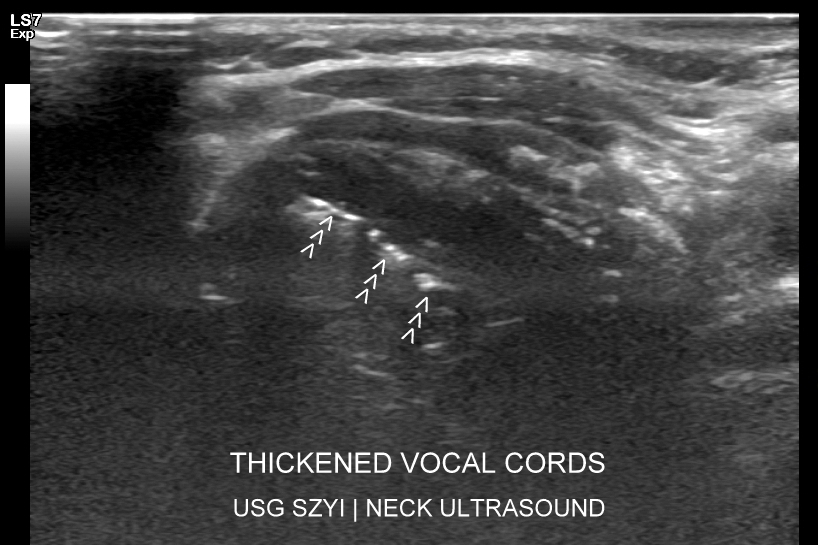

Badanie USG tarczycy we Wrocławiu oraz rozszerzone badanie USG szyi wykonają Państwo w prowadzonej od 2011 r. przez dr Tomasza Szczepańskiego Interdyscyplinarnej Pracowni Ultrasonograficznej. Służymy pomocą w przypadku potrzeby zaawansowanej diagnostyki USG guzków tarczycy, chorób zapalnych i autoimmunologicznych gruczołu tarczowego (choroba Hashimoto, choroba Gravesa-Basedova), oceny gruczolaków przytarczyc, a także w przypadku pojawienia się innych schorzeń takich jak guzy krtani, porażenie fałdów głosowych, torbiele szyi, powiększenie węzłów chłonnych, kręcz szyi. Badania USG tarczycy oraz USG szyi wykonujemy u dzieci i u dorosłych. Aktualnie diagnostykę USG i MPUS tarczycy oraz szyi u dr Szczepańskiego prosimy umawiać do Pracowni USG w następujących ośrodkach medycznych:

Dlaczego przy badaniu USG gruczołu tarczowego warto jednoczasowo wykonać USG szyi? Rozszerzone badanie USG ocenia kompleksowo narządy i struktury obszaru sąsiadującego z tarczycą, w którym to mogą lokalizować się różnorodne schorzenia. Przykładowo w przypadku wykazania guzków w tarczycy wskazana jest ocena lokalnych węzłów chłonnych, a w razie stwierdzenia stanu zapalnego miąższu tarczycy warto pod kątem chorób autoimmunologicznych ocenić także miąższ ślinianek. W obrębie szyi pojawiają się również takie choroby jak torbiele szyi, ropnie i zapalenia (np. pochodzące od zębów), gruczolaki przytarczyc, nowotwory (np. mięsak, kłębczak); napotkać można patologie w zakresie układu mięśniowo-szkieletowego (np. kręcz szyi, urazy splotu barkowego). Przeprowadzając USG szyi ocenia się także ślinianki, w których występować mogą zapalenia, kamica, czy guzy.